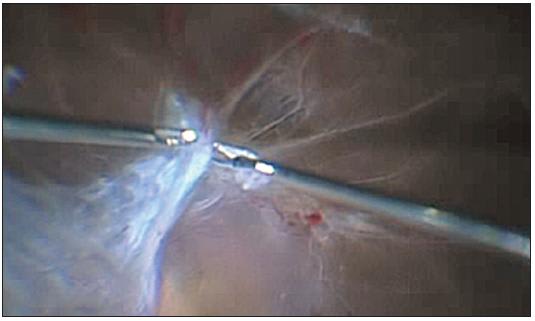

In addition, the largest advantage of chandelier endoillumination is the improved ability of performing bimanual intraocular manipulation for challenging cases. In patients with combined traction and rhegmatogenous retinal detachment with extensively adhesive fibrovascular membranes, we usually use a membrane forceps with a 25-g vitreous cutter to grasp and dissect the broad sheet of fibrovascular membranes. Under panoramic viewing, the membrane forceps allows us to engage easily the edge of the membrane to introduce more easily the blunt tip of the cutter into the tight spaces between the detached retina and adherent membranes (Figure 4). The combination of forceps with curved scissors can be another option for creating spaces between the fibrovascular membrane and its tightly adhered detached retina (Figure 5).

Figure 4. Bimanual dissection of a fibrovascular membrane. The membrane forceps allows us to engage easily to the edge of the membrane to introduce more easily the blunt tip of the cutter into the spaces between the detached retina and adherent membranes.

Figure 5. The combination of forceps with curved scissors can be another option for creating the spaces between the fibrovascular membrane and the detached retina when the membrane is tightly adhered to the detached retina.